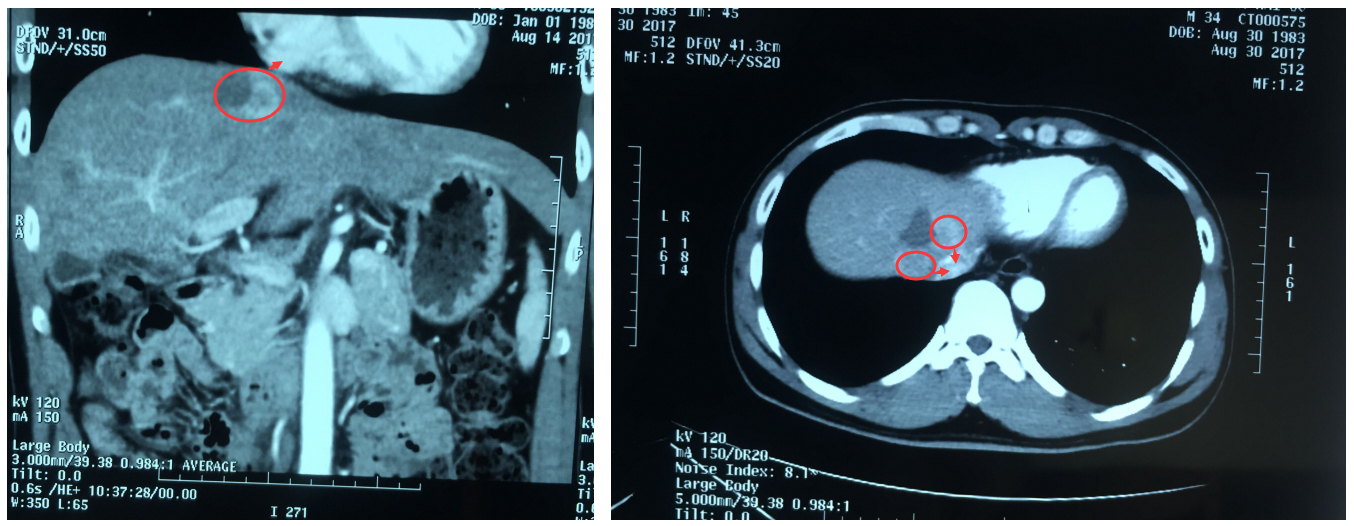

更让人心痛的是,经检查,他的肝脏肿瘤位置非常特殊:不仅位于膈脚下腔静脉旁,而且距离心脏只有1.5cm,不宜再行传统外科手术。常规肿瘤消融术又不足以彻底消灭肿瘤,那该怎么办呢?

▲患者肝脏肿瘤距离心脏1.5cm,位于膈脚下腔静脉旁

2017年9月1日上午,阮先生在气管插管全身麻醉状态下进行了纳米刀消融术,由白海山主任主刀,在CT扫描定位下,将两支电极针穿刺至患者肝脏肿瘤内进行消融。

白海山介绍说:“患者的肿瘤位置特殊,穿刺难度较大,术中容易引发出血、严重心律失常,心脏骤停等问题,广州现代医院专家组为此进行了认真的术前会诊,加上经验丰富的手术、麻醉团队默契的配合,整个过程患者生命体征平稳,手术顺利完成。术后患者被送往ICU进行观察,接下来需要配合后续综合治疗。

▲术后CT扫描见肿瘤消融完全